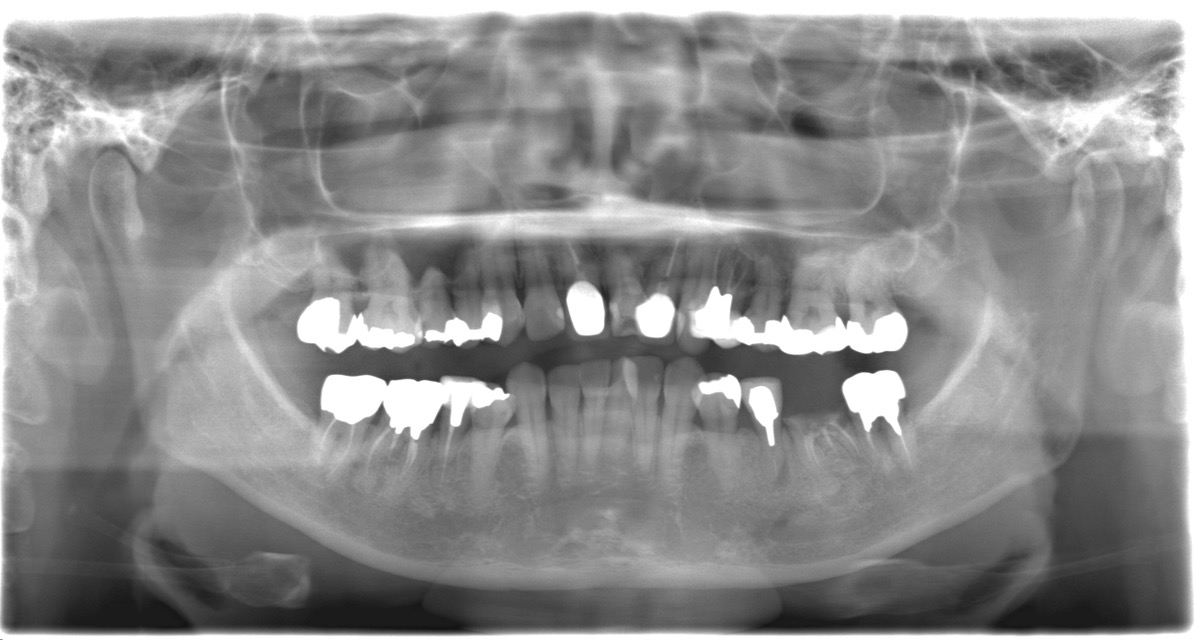

レントゲンやお口の中の状態を確認したうえで、